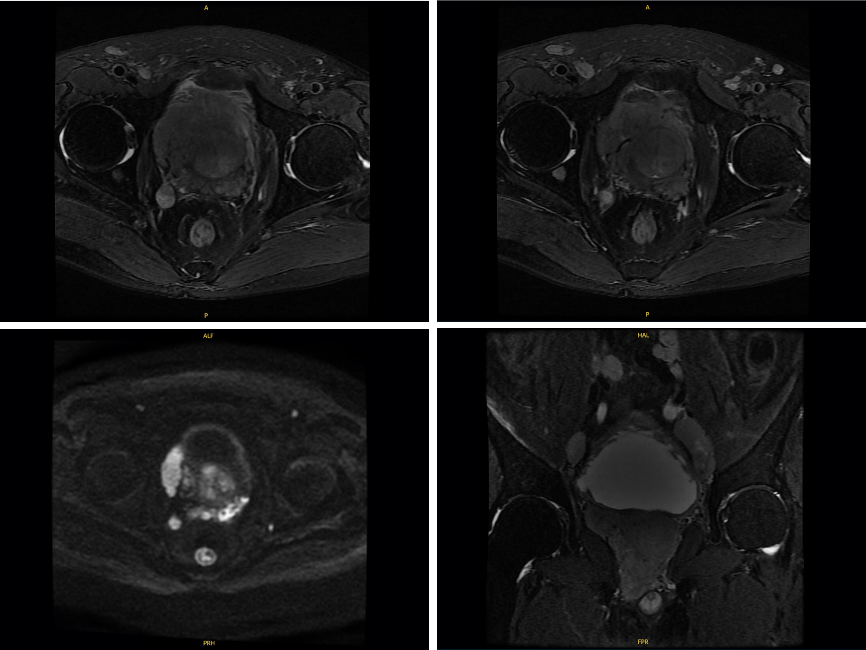

MRI:

T1WI示前列腺体积显著增大,并向膀胱内突出,5.9 × 7.2 × 6.9 cm,体积147 mL;T2WI示前列腺中央带及周围带多发大小不等结节影,前列腺包膜连续性中断,侵犯膀胱及精囊;双侧髂血管旁及双侧腹股沟可见多发增大淋巴结,部分融合。

图 1 2022年12月23日前列腺癌MRI平扫